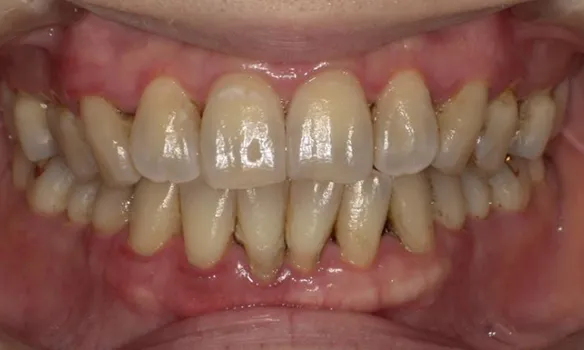

審美歯周病治療

見た目も美しく

歯周病治療を行うと歯茎が下がったとよく聞きます。残念ながら、炎症が長期に渡り存在していた歯茎や、重度歯周病では、治療を行うことにより歯茎が下がり炎症が除去されると歯茎が下がってしましやすいです。そういった場合、セラミックス治療を行うことで審美的に改善を図ることがあります。

また、歯周病はないのに、歯茎が下がってしまうことによる審美性が損なわれてしまう病気があります。そのような場合、歯茎の移植などを行うことにより、歯を削ることなく審美性を改善させることができます。 -